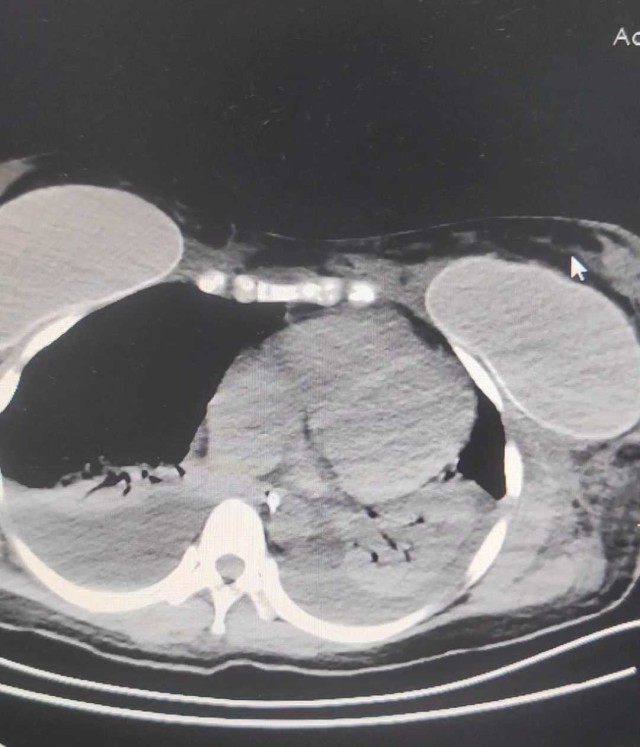

整个右侧胸腔被滚烫的铝水烧穿,多根肋骨骨折、碳化、坏死,背腹部和面部也有大面积烧伤……右肺完全暴露在外,被压缩到只剩一半的体积。这样的病人,还救得活吗?300℃ 铝水烧了 10 分钟,整个右胸都烧穿了时间拨回到 2024 年 9 月 26 日,下午 15 点,救护车的警笛声撕破了浙江大学医学院附属第二医院(文内简称「浙大二院」)解放路院区的平静。警笛声由远及近,停在了急诊的门口。不多时,一群人冲进急诊。「300 多度的铝水烧了 10 分钟,整个右胸都烧穿了!」负责转运的同事几乎是咆哮着喊出这句话。急诊医学科的许永安主任医师看到患者情形时,心下一惊。本该完整的右侧胸腔,现在成了一个焦黑的大洞,大